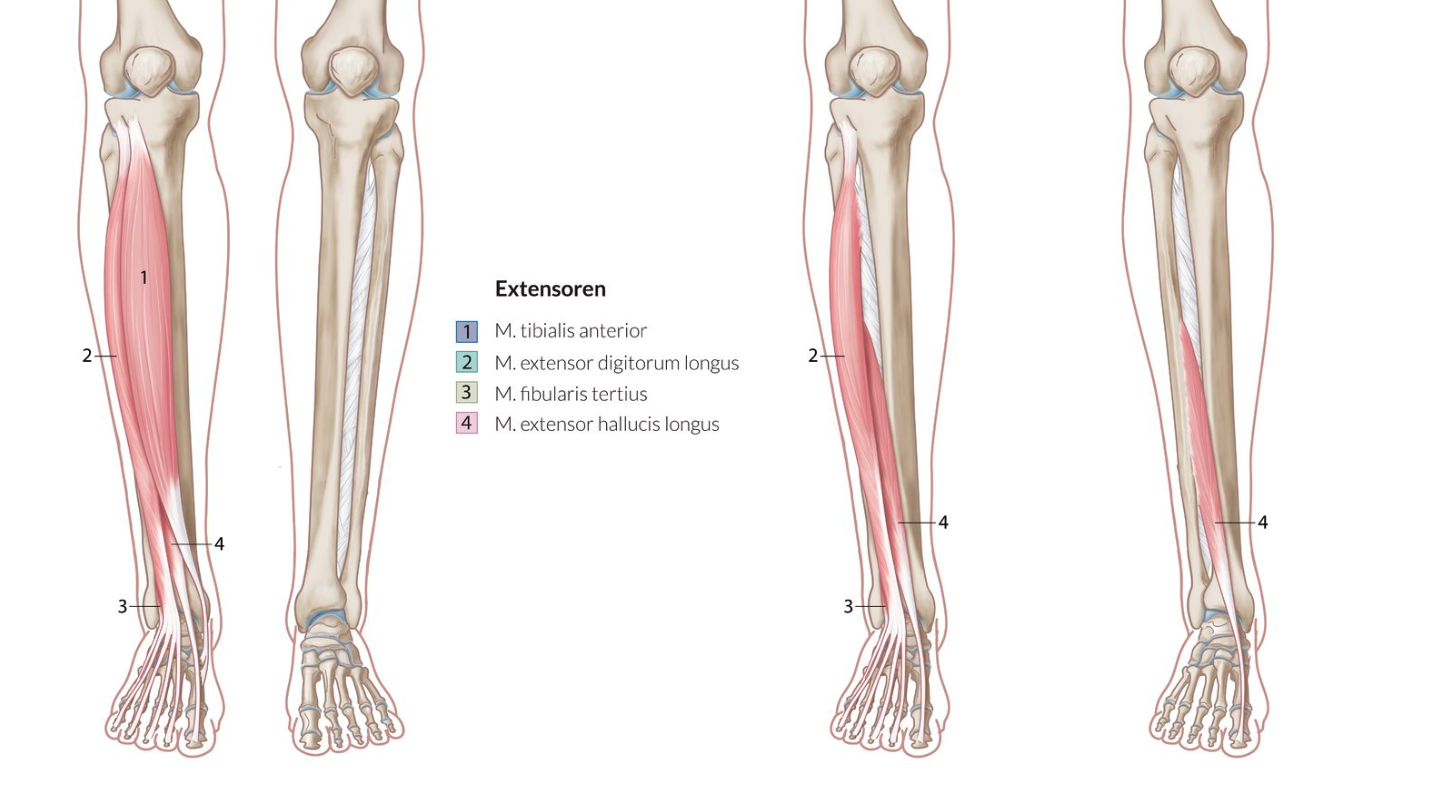

26. Muscle weakness often leads to clinically visible gait abnormalities.

Weakness or failure of which muscle group(s), acting on the upper ankle joint, leads to a steppage gait (also known as high-stepping or stork gait)?

A. Dorsal extensors

B. Plantar flexors

C. Pronators

D. Supinators

E. Pronators and supinators